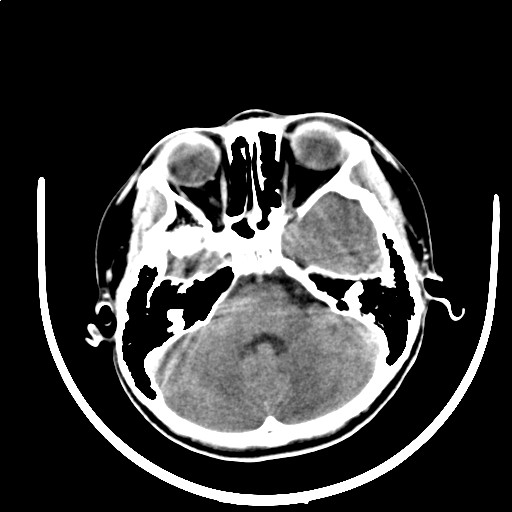

标题: PED3416:F,12Y,智力下降,学习成绩差,8个月时发过高烧。

不出意外的话,患者面部也应该有血管瘤的改变。符合颅颜面血管瘤的表现。

我仔细看过,患儿面部没有血管瘤改变。

右侧大脑发育不良伴动静脉畸形。

颅面血管瘤病(sws)。

右侧半球萎缩,软化,多量脑回样钙化,考虑颅面血管瘤病,建议dsa检查

右侧半球萎缩,软化,多量脑回样钙化,同侧颅盖板障增宽,考虑颅面血管瘤病,建议dsa检查与化脓性脑膜炎后遗改变鉴别。